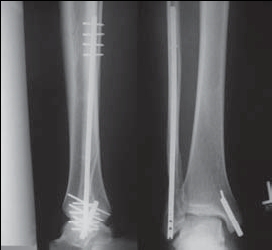

Если и оперировать, то, наверное, целесообразно бы поставить IP-XSL (long nail). И косметический дефект минимальный, и нагрузка сразу и удалять нет особой необходимости.

Перелом малоберцовой кости есть, понятно. Но боли в голеностопном суставе! А как вы изучали патологическую подвижность стопы? Есть стрессовые снимки?

Вопрос, который возникает у меня при виде таких снимков,- "Какой механизм травмы?"

Если это прямой удар, то кроме перелома м,б кости и ушиба мягких тканей ничего нет.

Если механизм непрямой, т.е. подворачивание (ротация) стопы, то это повреждение надо классифицировать как нестабильный перелом лодыжек (44 С.2) с повреждением синдесмозных связок.... Да, на обычных рентгенограммах можно

видеть идеальный голеностопный сустав

здесь пропускаем повреждение Maisonneuve...

Здесь как раз тот случай, когда рентгеновский снимок скрывает главную проблему. "Ходит, прихрамывая на правую ногу, отмечает боли в правом голеностопном суставе" По описанию клиника типичная для повреждения голонестопного сустава - синдесмоза.

При проксимальных переломах малоберцовой автоматически необходимо подозревать повреждение синдесмоза - Maisonneuve Fracture.

Описанное в 1840 году Maisonneuve повреждение характеризуется тем, что при фиксированной наружной ротации стопы повреждается передняя фибуло-тибиальная связка, часть синдесмоза, с переломом медиальной лодыжки и без, дальше разрыв продолжается по межкостной мембране и спиральный или косой перелом малоберцовой происходит выше.

Глубокоуважаемый Якоб Одесскиий! Увы, но из снимков голеностопа возможно предоставить только приложенный, боковая проекция в первичном сообщении. Спасибо за указание возможного повреждения голеностопа, но напомню, что главный вопрос топика о неоходимости синтеза малоберцовой кости ПЛАСТИНОЙ. В примерах показанных Джолдасом Кульджановым пластина и вообще вмешательство в область перелома не используется, т.е. его позиция ясна. Вы можете что-то добавить?